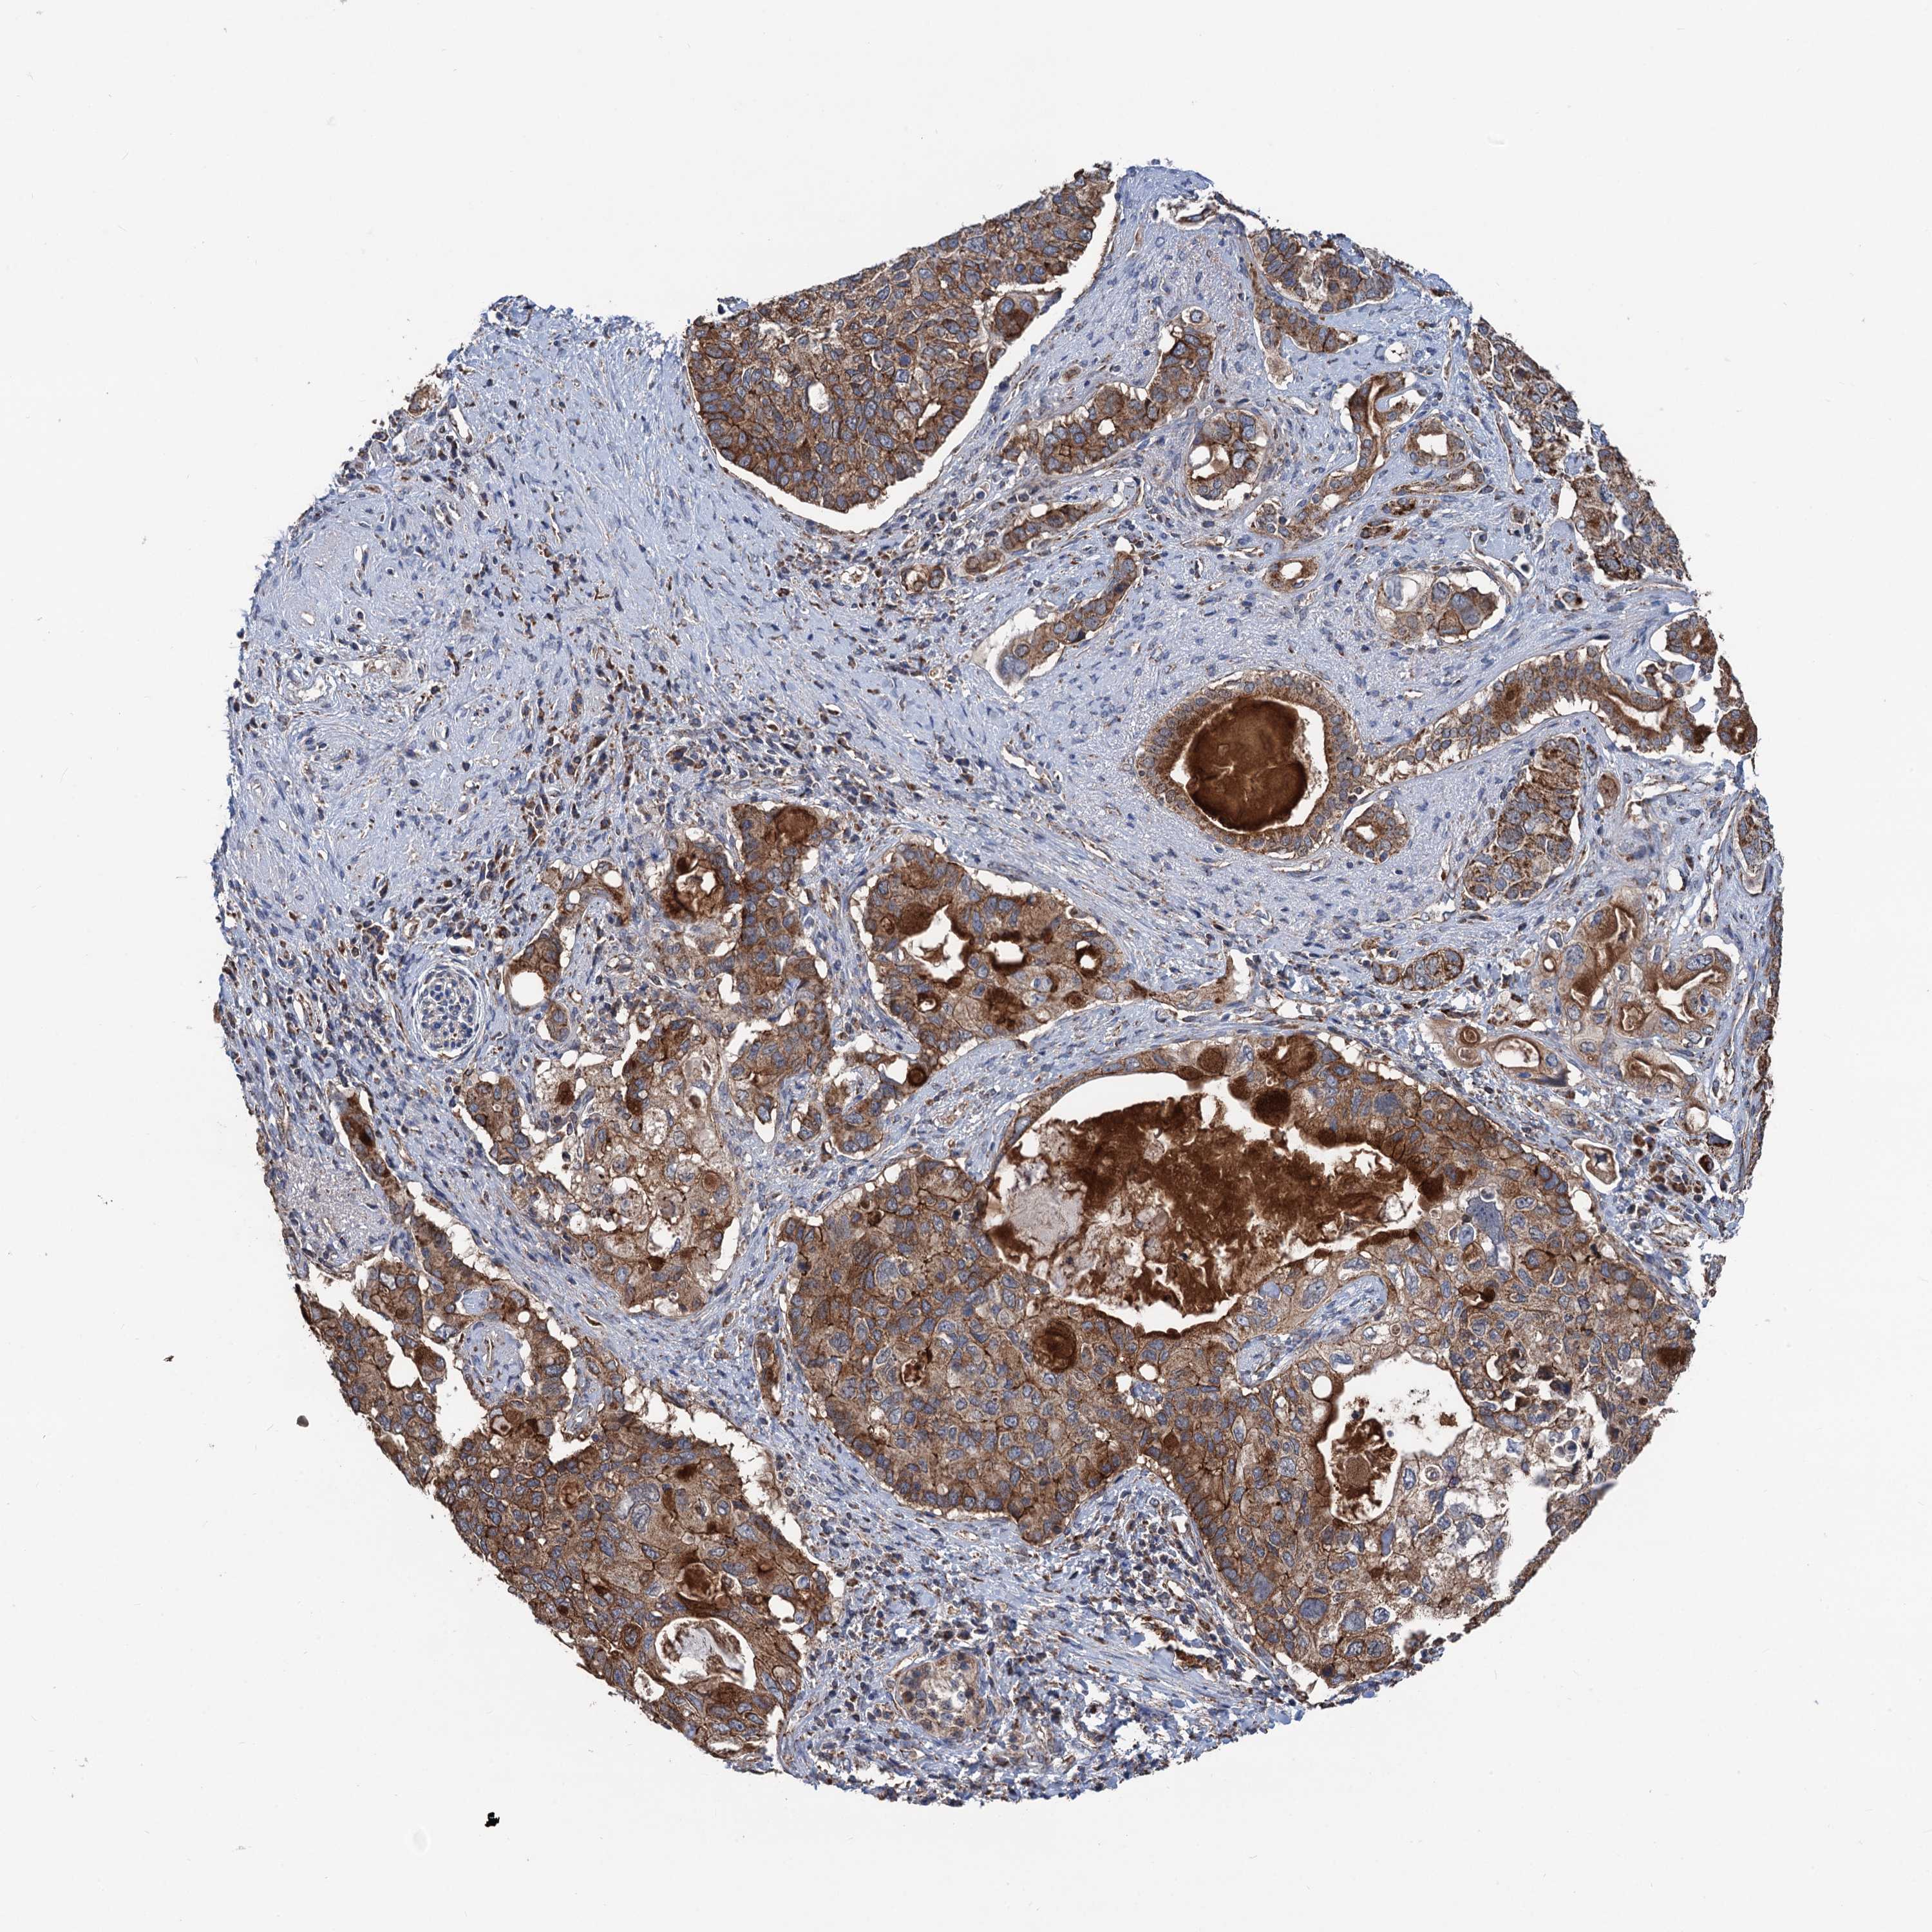

PANCREATIC CANCER - Protein expressioni

A mouse-over function shows sample information and annotation data. Click on an image to view it in a full screen mode. Samples can be filtered based on level of antibody staining by selecting one or several of the following categories: high, medium, low and not detected. The assay and annotation is described here.

Note that samples used for immunohistochemistry by the Human Protein Atlas do not correspond to samples in the TCGA dataset.

Antibody stainingi

Antibody staining in the annotated cell types in the current human tissue is reported as not detected, low, medium, or high, based on conventional immunohistochemistry profiling in selected tissues. This score is based on the combination of the staining intensity and fraction of stained cells.

Each image is clickable and will lead to virtual microscopy that enables deeper exploration of all samples and also displays staining intensity scores, fraction scores and subcellular localization as well as patient and tissue information for each sample.

Antibody HPA041423

Staining

High

Medium

Low

Not detected

Intensity

Strong

Moderate

Weak

Negative

Quantity

>75%

75%-25%

<25%

None

Location

Nuclear

Cytoplasmic/membranous

Cytoplasmic/membranous,nuclear

Adenocarcinoma, NOS